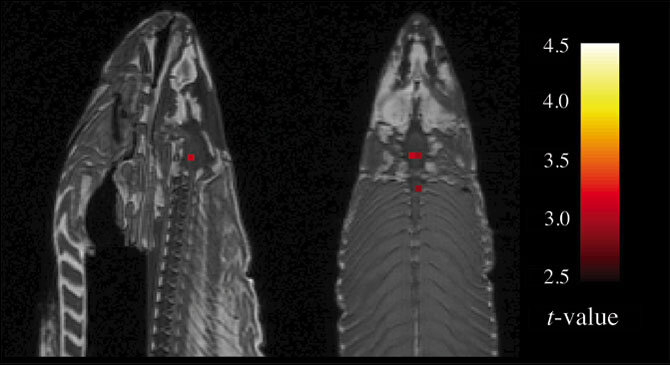

Что может рассказать мертвый лосось?

Шнобелевская премия 2012 в области неврологии была присуждена Крэйгу Беннетту с соавторами за очень необычную публикацию. В чем же там было дело читайте в конце статьи. Но результатом этого происшествия стало понимание, что даже современные методы исследований могут давать ложноположительные результаты.

То самое МРТ!

Крэйг Беннет с соавторами сканировали мозг мертвого атлантического лосося. Ими было обнаружено, что фМРТ показывало мозговую активность. Хотя, конечно, любой биолог скажет, что никакой электрической активности у мёртвого мозга нет и быть не может. Поэтому так необходима стастистическая обработка результатов исследований и проведение таких исследований на большем количестве испытуемых, ведь никакой метод не застрахован от того, чтобы обнаружить "мозговую активность мёртвого лосося!"